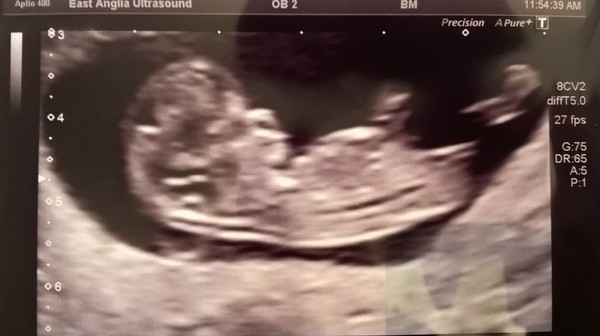

Just been for my 12 weeks scan. Everything was fine and it was amazing to see baby moving around so much!! Very happy!! X

Yay billy amazing scan picture, Aww so lovely, really happy for you x

Congrats on your scan news billy. You must be the first one to have had a 12 wk scan.

Thanks everyone! Due date is 2nd May. So I'm 11w2d today. I had a scan at 8 weeks too and am amazed how different it was today. Seeing baby move and stretching its arms and legs out was amazing!

I was swaying towards thinking its a boy.. But I saw something on nub theory and after reading that and seeing scan I'm now thinking girl! We find out 18th December... Nice Christmas present!

Aaww lovely scan pic billy we have the same due date!!

Here's mine from my private scan at 10+6. Can't wait to see him/her again for the 12 (or should I say 13!) week scan on 27th.

I've also been seeing if I can work out the gender but don't quite understand where to look for the nub or if it's even visible on this picture!

Frozen that's lovely :) so happy for you and Billy. And good to see your pic as I'll be 10+6 for my scan...not sure why it's so early but will def go with it! haha! Your pic is still really good for 10+6, hoping mine will be too!